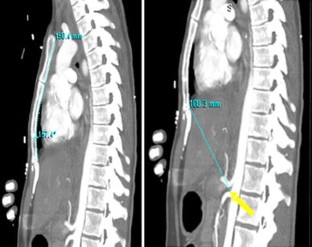

Fig. 3